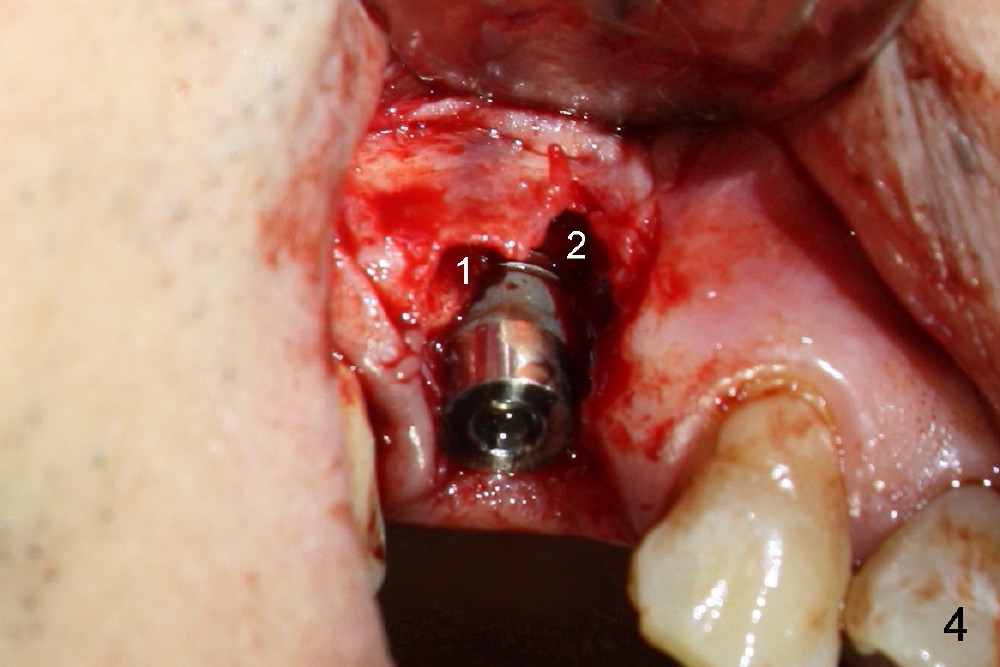

Buccal flap is raised (Fig.4) for bone graft and collagen membrane. The graft is autogenous, harvested using the reamers mentioned above and mixed with Bicon Synthograft.